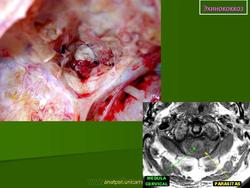

Патоморфология. Эхинококк — пузырь с довольно толстой слоистой хитиновой оболочкой, наполненный прозрачной жидкостью, содержащей янтарную кислоту. Различают эхинококк однокамерный и многокамерный, или альвеолярный. Эхи'нококк вызывает в мозге реактивное воспаление, что приводит к образованию плотной капсулы, наружные слои которой инфильтрированы лимфоидными, плазматическими и эозинофильными клетками. Располагается он чаще всего в глубине полушарий. Величина эхинококка колеблется от горошины до куриного яйца. В некоторых случаях он растет кнаружи и, выходя на поверхность мозга, может узурировать кость.